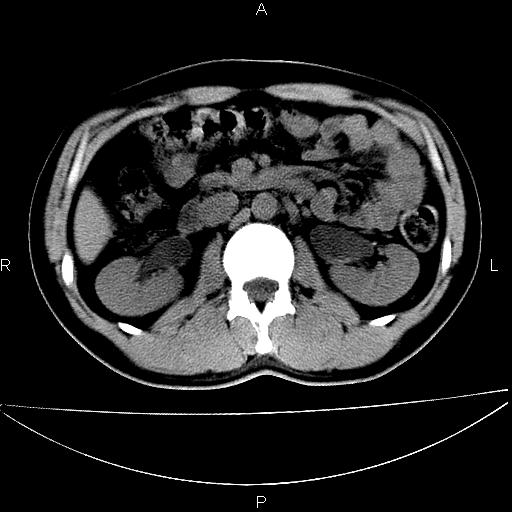

男 25岁 自述 尿频尿急,排尿困难20多天.无腰痛, b超说左肾盂轻度积水,左输尿管上端扩张.未见结石影. ct我看双侧肾盂轻度积水,双输尿管上端都扩张,大家看看能看见结石吗?

双输尿管扩张下端未见高密度结石和输尿管晕轮征,不好说是结石.增强后如何?

双肾轻度积水,未见明确结石,薄层对结石检出率较高。

双侧输尿管上端扩张,未见明确结石,可进一步ivp检查。